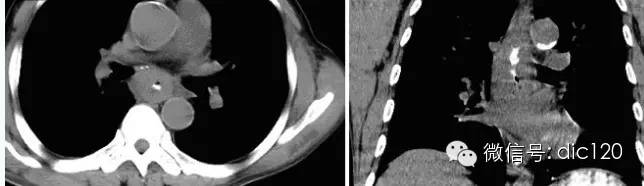

【影像表現】 CT:表現現為食管壁明顯增厚,管腔狹窄;食管與周圍結構分界不清食管吞鋇:食管中段充盈缺損,管腔不規則狹窄,管壁僵硬,粘膜糾集破壞,與正常食管壁分界清晰。

【診斷】 病理診斷:食管(中下段)高-中分化鱗狀細胞癌,侵及食管壁全層。(圖1.2)